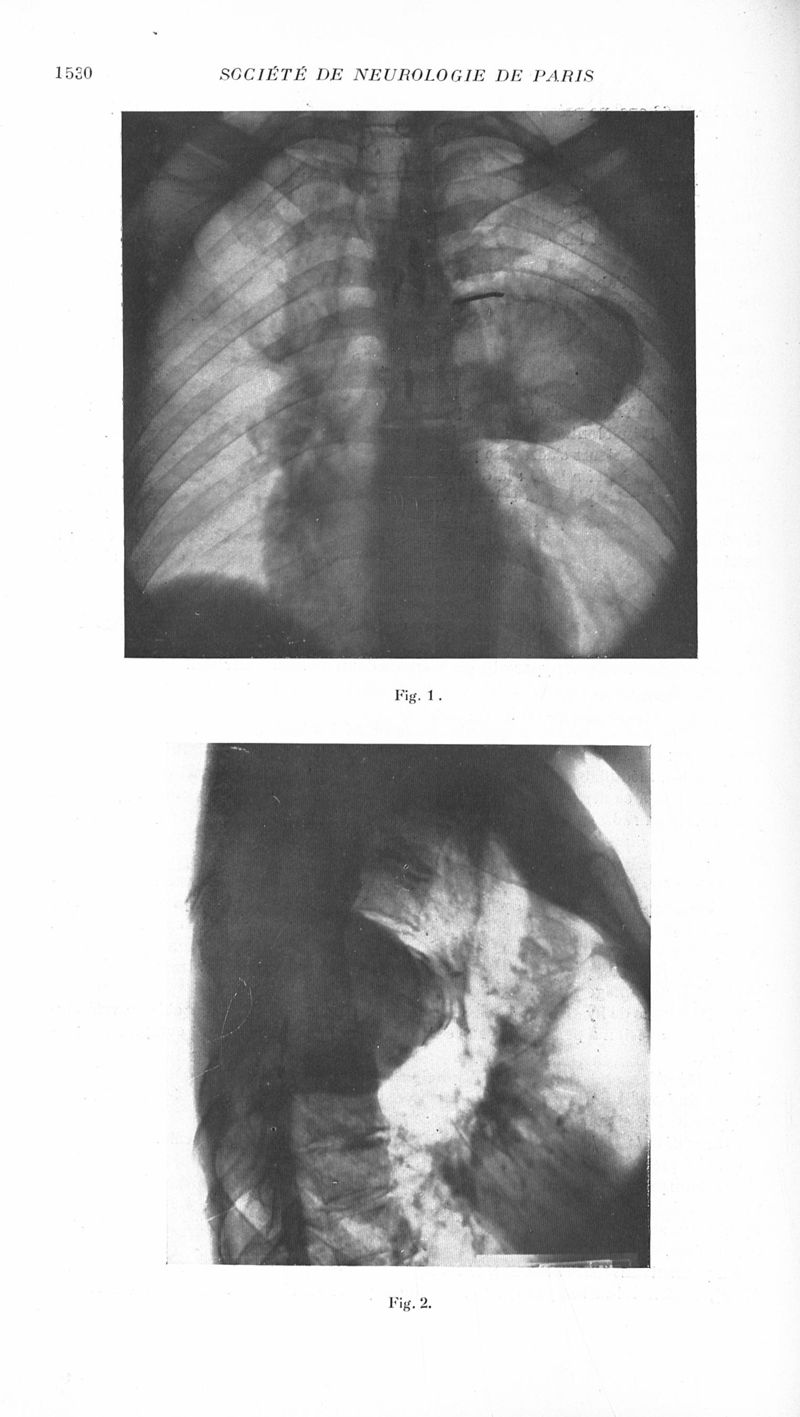

Revue neurologique

1936, vol 1. - Paris : Masson , 1936.